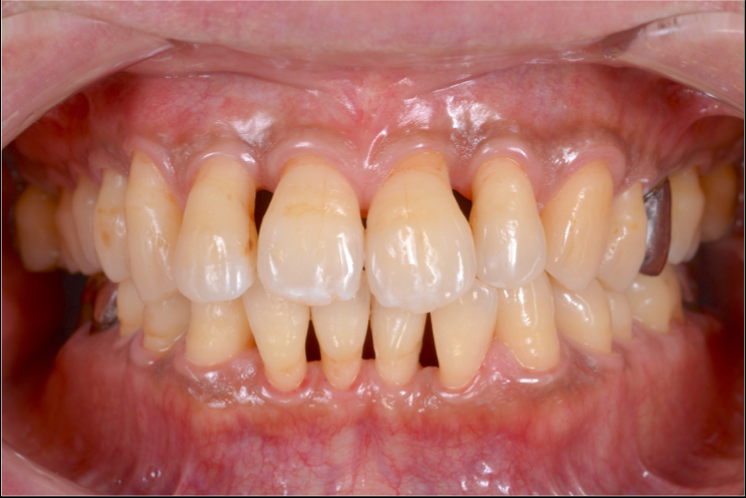

治療例

重度歯周病の症例